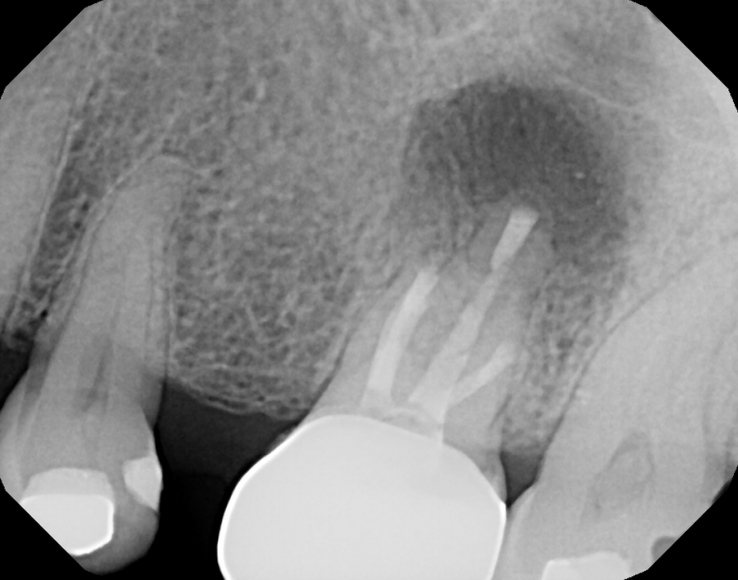

#30 NS-ReTx